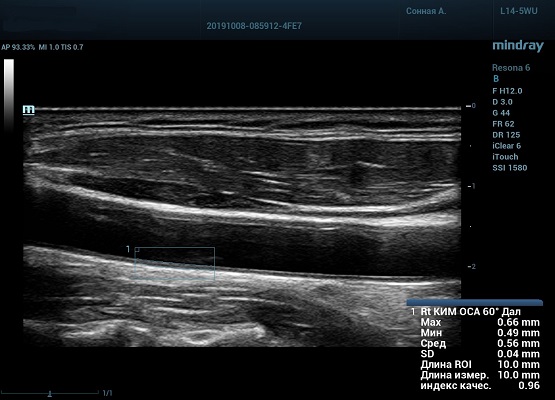

На сегодняшний день измерение IMT происходит автоматическим путем при использовании функции AUTO-IMT. Необходимо указать прибору зону интереса, стандартной длиной (1 см), в которой происходит отслеживание кромок и выдача максимального, среднего и минимального значения. УЗИ аппараты компании Mindray среднего, экспертного и премиального класса снабжены данной функцией и позволяют контролировать не только полученные значения, но и оценить точность измерения кромки в конкретной зоне по индексу качества. Используя индекс качества, легко решить, можно ли использовать полученное значение.

Форма отчета стала удобной: в единой таблице сводятся измерения левых и правых артерий, указываются все значения с автоматическим расчетом общего среднего показателя. Если один из показателей измерения резко выбивается и считается недостоверным – его можно исключить из расчета.